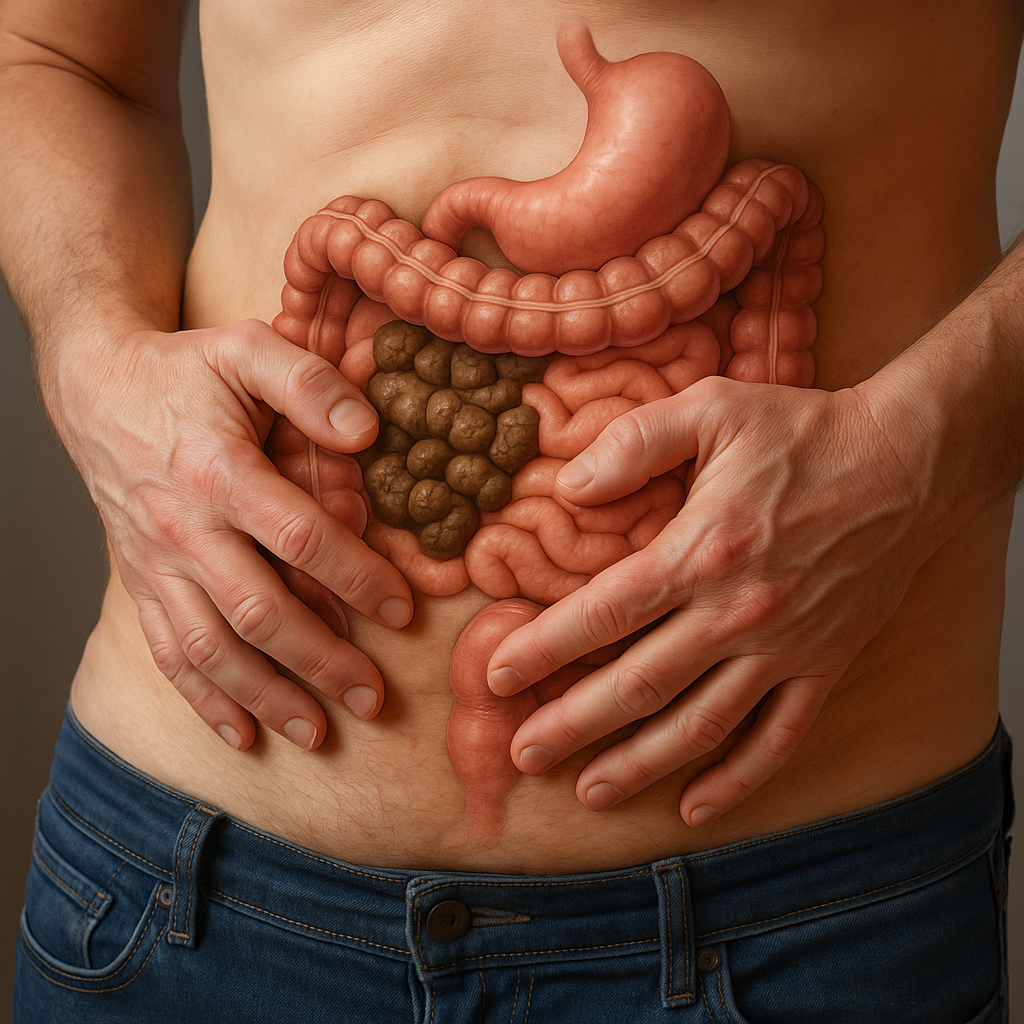

# Anal and Digestive